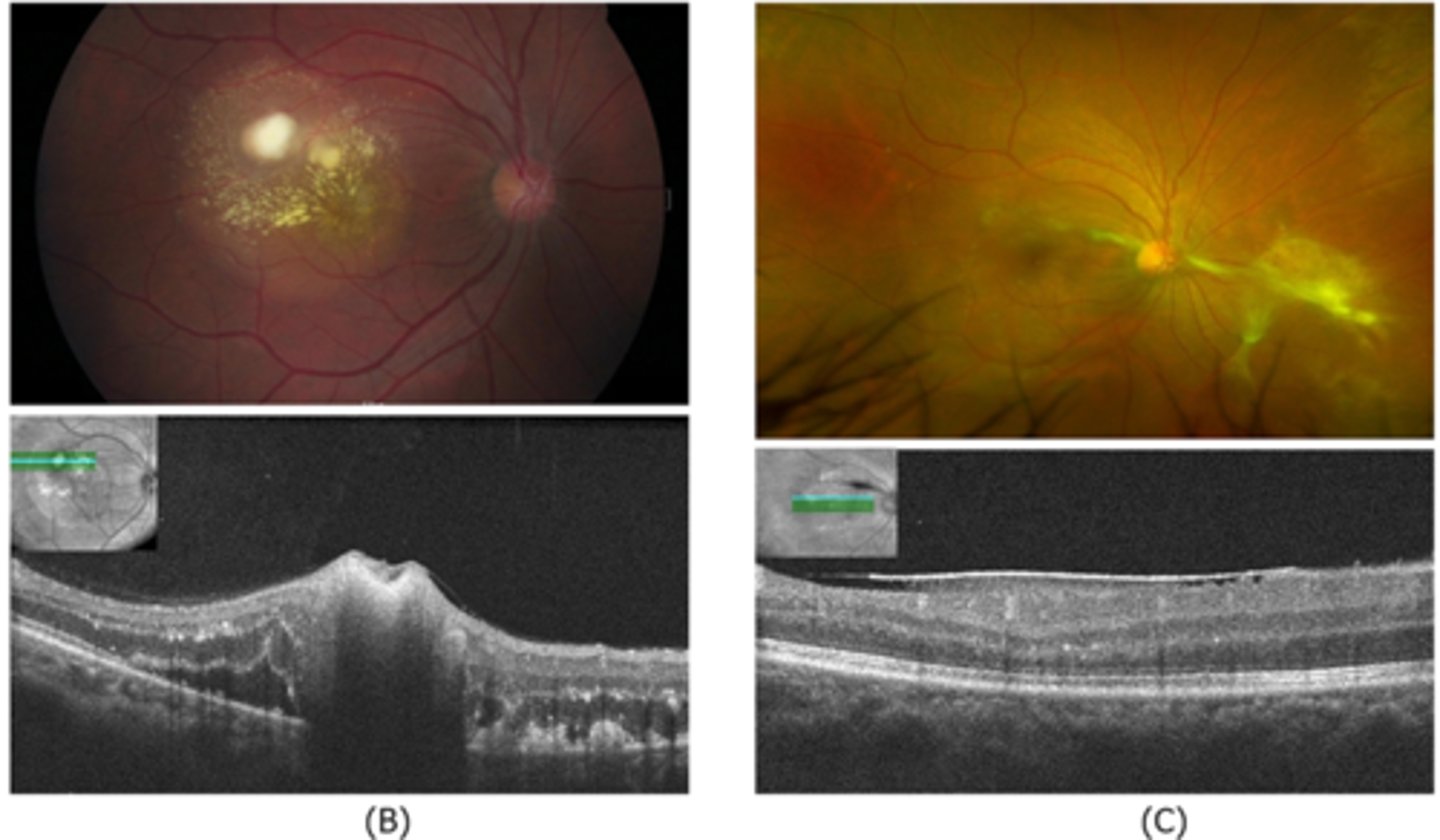

What finding of toxoplasmosis is seen in A/B?

retinitis turns into hazy scar with nerve pallor

What finding of toxoplasmosis is seen in C/D?

scarring overtime with VA loss/scotoma

What is seen in toxoplasmosis with OCT?

acute = retinitis = inflam, thickening of layers

acute = vitritis = dots and haze vitreous

chronic = necrotizing atrophy = scarring, thinning

What findings of toxoplasmosis are seen here?

retinal vasculitis

exudative scar

focal, hazy vitritis and retinitis

What findings of toxoplasmosis are seen here?

latent scars